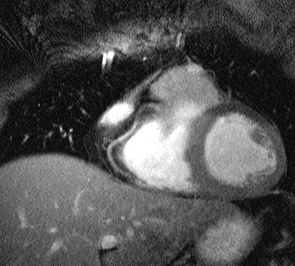

inspiration for subsequent scans. Two corresponding images

of the RCA of one volunteer are shown below.

Figure 3. The RCA of one healthy volunteer for end-expiration

(left) and inspiration (20mm shift of the right hemidiaphragm) (right).